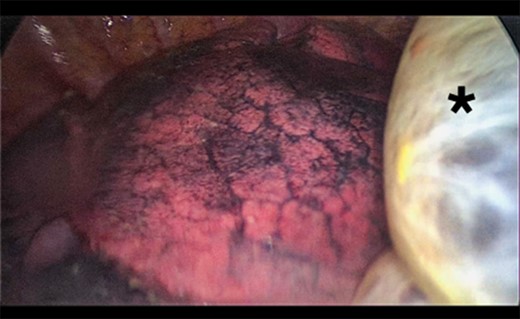

A 73-year-old male patient with a clinical history of COPD, lung emphysema and a 30-year smoking history was admitted to the ED due to a 24-h clinical picture of dyspnea immediately following a sudden bout of dry coughing. Physical examination showed a dyspneic patient, tachypnea of 25 rpm, heart rate of 85 bpm and blood Pressure of 135/75 mmHg along with central cyanosis. Chest exam showed a hyper-resonant right hemithorax along with reduced breath sounds. Initial chest X-ray revealed a large right-sided pneumothorax (Fig. 1). A right chest tube was placed in the ED. Emergency echocardiogram had no significant findings and spirometry showed suspected patterns of obstruction. Following patient stabilization, a high-resolution chest computed tomography (HRCT) was performed revealing extensive pan lobar emphysema throughout both lungs, para septal emphysema in both the anterior upper lobes and herniation of a left lung bullae through the anterior mediastinal pleura along with a right-sided pneumothorax with the chest tube in place with persistent air space (Fig. 2). The patient was taken to surgery where a right video-assisted thoracoscopic (VATS) approach showed severe lung emphysema and a contralateral herniated left lung bulla through the mediastinal pleura anterior to the pericardium (Fig. 3). Right pleurodesis was performed using Talc and a left posterior thoracoscopy showed a severe emphysematous left lung with a lingular herniated bulla to the right hemithorax through an anterior mediastinal pleural defect along with pleural adhesions (Figs 4 and 5). Thoracoscopic hernia reduction was performed along with bullectomy using 60 mm mechanical sutures (Fig. 6). Chest tubes were removed on POD 3 (right) and POD 4 (left). The patient had significant respiratory improvement and was discharged on POD 5.

Thoracoscopic view from left side of thoracoscopic bullectomy.